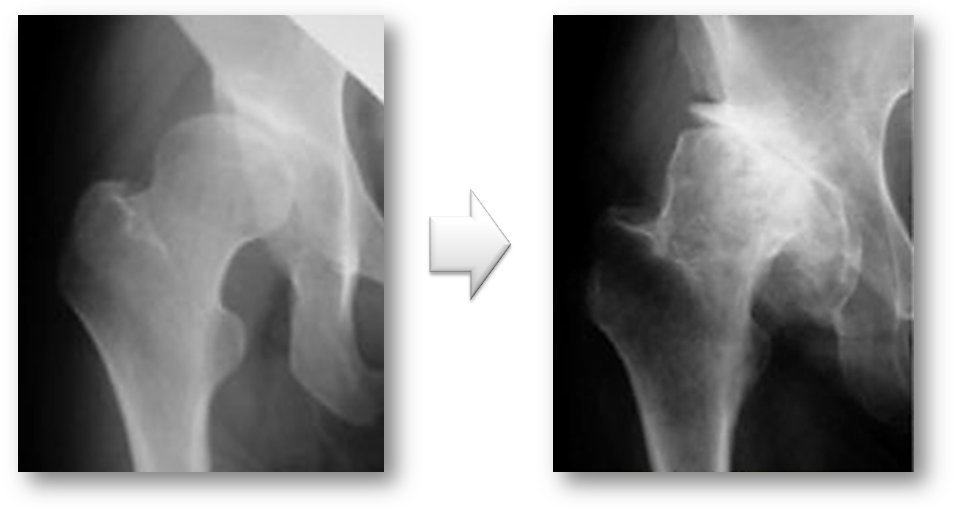

変形性股関節症には、一次性と二次性があります。一次性は、長い年月を経てあるいは関節の使いすぎによって軟骨が消耗して起こります。二次性は、乳児期の股関節の脱臼や発育不全などの臼蓋形成不全によって早期から起こる変形性股関節症です。

レントゲンで見ると一次性は、正常な股関節が長い年月や股関節の使い過ぎによって軟骨が消耗して変形性股関節症が発症します(図7)。二次性は、元々臼蓋形成不全により体重がかかる部分が限られており早期なら軟骨が消耗し変形性股関節症になります(図8)。

図8. 二次性の変形性股関節症

乳児期の股関節の脱臼や股関節の発育が悪いこと(臼蓋形成不全)が原因で起こる。